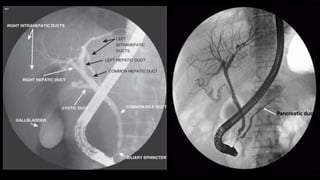

PERCUTANEOUS TRANSHEPATIC

CHOLANGIOGRAPHY (PTC)

Radiographic visualisation of

biliary duct system.

• Ultrasound / CT – assessing the biliary anatomy and cause and level of

obstruction.